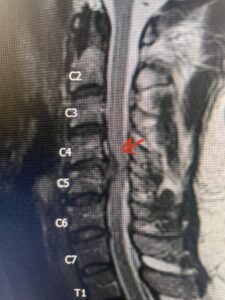

Fig 2a Sagittal and axial T2 weighted cervical MRIs demonstrating large C4 5 herniated disc with spinal cord compression red arrows

Fig. 2a Sagittal T2-weighted cervical MRI demonstrating large C4-5 herniated disc with spinal cord compression (red arrow)